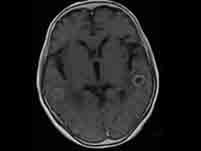

问题 肺癌的肺外表现有()

选项 A.杵状指和肺性肥大性骨关节病 B.脑转移 C.内分泌紊乱症状 D.神经肌肉综合征 E.骨转移

答案 ACD